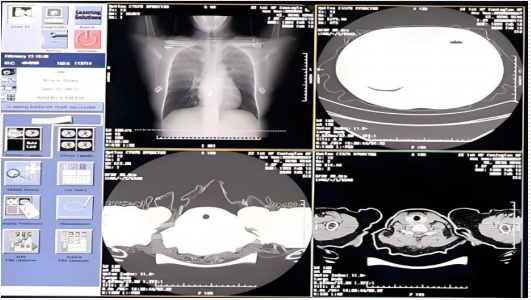

智慧医疗 - 医学影像识别:基于深度学习等人工智能技术的X光、核磁、CT、超声等医疗影像多模态大数据的分析技术,提取二维或三维医疗影像隐含的疾病特征。

- 医学影像识别:基于深度学习等人工智能技术的X光、核磁、CT、超声等医疗影像多模态大数据的分析技术,提取二维或三维医疗影像隐含的疾病特征。